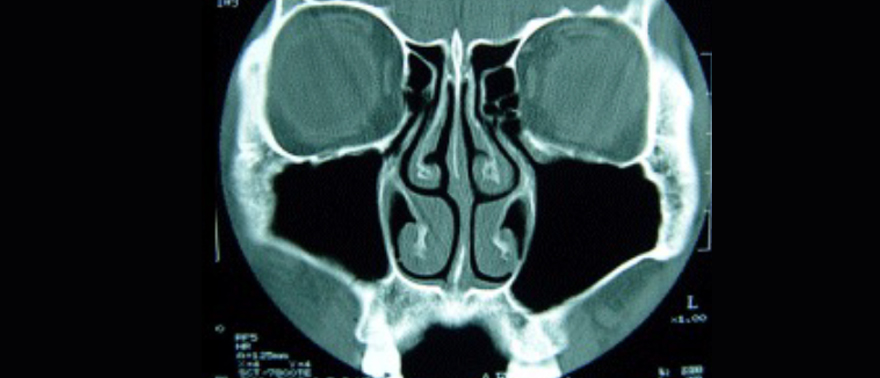

비후성비염 코 CT 소견